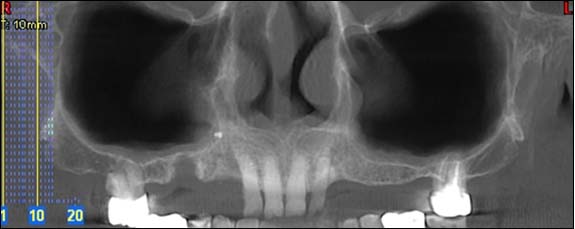

EXAMENS TOMOGRAPHIES VOLUMIQUES TYPE SCANNER OU CÔNE BEAM :

Dernière technologie à notre disposition, cette technique permet de voir en 3 dimensions des images de votre bouche et de mettre en évidence des pathologies ou des anomalies que les autres techniques ne permettent pas d’objectiver.

Reconstruction panoramique

Reconstruction coronale